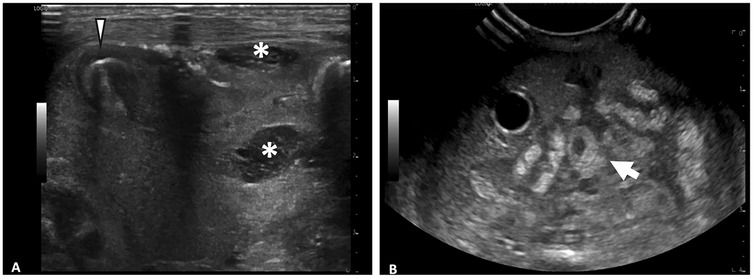

The types of ultrasound transducers used included low frequency 3–10 MHz micro-convex, low frequency 2–9 MHz linear, high frequency 6–15 MHz linear, high frequency 8–18 MHz linear, and high frequency 4–20 MHz linear. Ultrasounds performed with linear, high-frequency transducers (>10 MHz) yielded higher numbers of HRF (median = 4, IQR 3–7) compared to those performed with lower-frequency transducers (≤10 MHz) (median = 1, IQR 0–2) (p < 0.001) (Figure 3). The AUS obtained with the higher frequency transducer had a higher resolution of intestinal wall architecture than with the lower frequency transducer, as shown in Figure 4.

Figure 4. Comparison of abdominal ultrasound images obtained with high frequency vs. low frequency ultrasound transducer. (A) Image obtained with 6–15 MHz linear transducer. Improvd spatial resolution of 6–15 MHz transducer allows for visualization of fine details such as septations within fluid collections (*) and layers of intestinal wall (arrowhead). (B) Image obtained with 3–10 MHz transducer. Echogenic loop of bowel (arrow) seen, however further evaluation of intestinal wall limited by decreased spatial resolution.

When stratified by patient weight, the impact of transducer frequency varied significantly. Neonates weighing <2 kg demonstrated a relatively greater difference in interpretability in exams performed with high vs. low-frequency transducers (median = 7, IQR 5–8 vs. median = 1, IQR 0–2, p = 0.005) (Figure 5A). Comparatively, in neonates weighing ≥2 kg, there was a relatively lower difference in interpretability (median = 3, IQR 2–4 vs. median = 1, IQR 0–2) (Figure 5B). Most notably, two neonates weighing 0.5 kg, who died with the surgical confirmation of SIP, had no HRF noted on AUS when a low-frequency transducer was used.